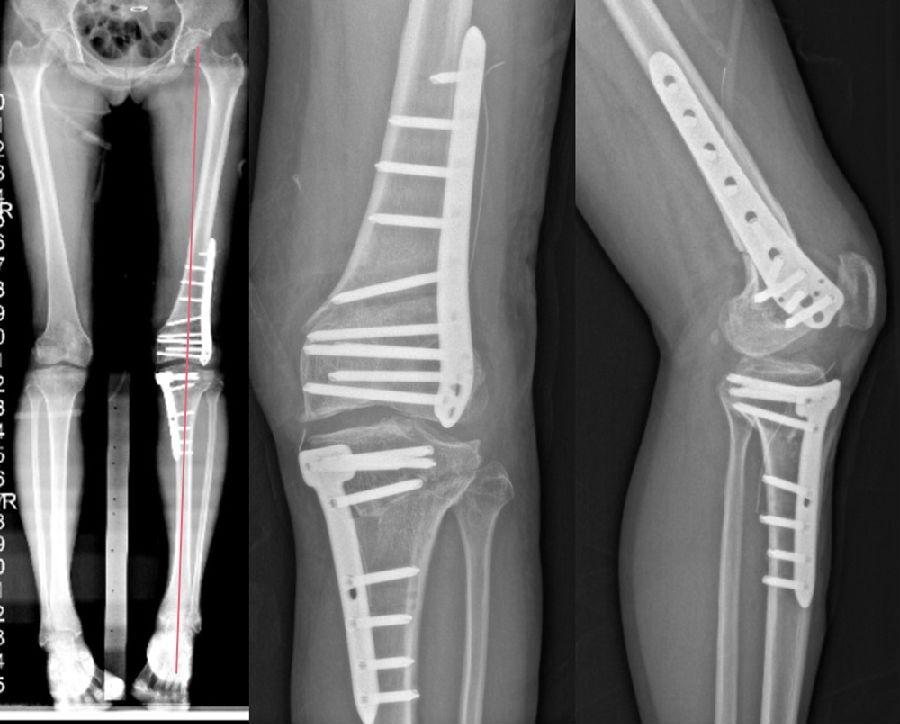

术前X线片

术前X线显示:

胫骨近端内侧角(MPTA):100°

股骨远端外侧角(LDFA):102°

关节线夹角(JLCA):3°

股骨远端后倾角(PDFA):85°

胫骨近端后倾角(PPTA):83°

术后X线片